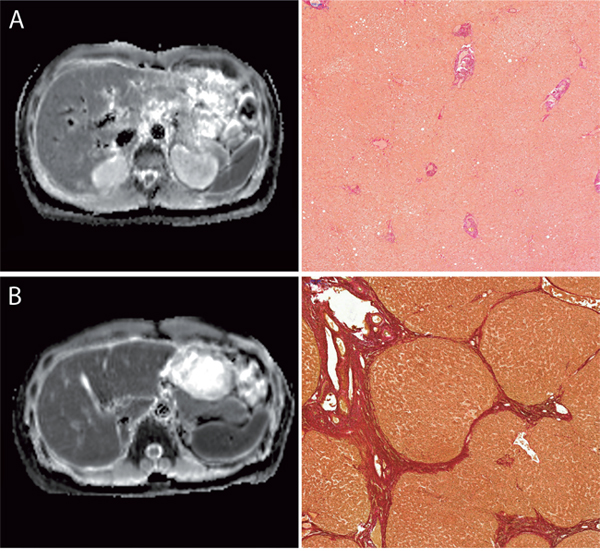

There was a significant difference in the mean ADC value between patients without liver fibrosis (ADC = 1123 ± 95.8 mm2/s) and patients with any stage of liver fibrosis/cirrhosis (ADC = 1010 ± 76.13 mm2/s; p < 0.001) (Figure 1).

Figure 1: Images comparing the ADC-Maps with corresponding histopathology images with the EVG staining. Figure 1 compares the ADC-Maps with corresponding histopathology from a patient with normal liver parenchyma (A) and from patient with end stage liver fibrosis (B). All images are with the same window level and center. The ADC-value of the liver parenchyma were as follows: (A) no liver fibrosis (Ishak 0), ADC: 859 mm2/s (B) advanced liver fibrosis (Ishak 5), ADC: 1128 mm2/s.